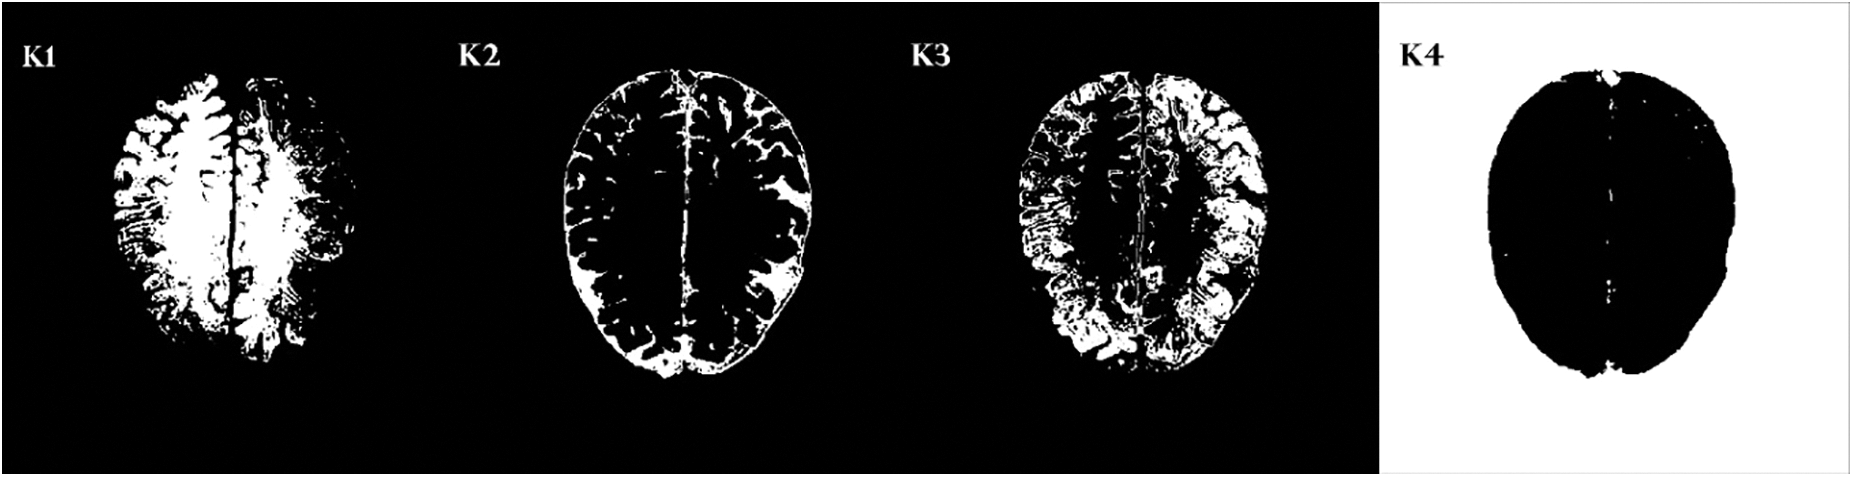

As discussed earlier, CMBs are minute particles having a tiny size and the trouble in detecting microbleeds is because of the presence of similar healthy cells. The k-mean clustering algorithm is also called hard clustering. This algorithm is simple and fast, but its limitation is that it cannot fragment CMBs very efficiently if it is malignant.

It depends on an iterative procedure that partitions the neuroimage into different clusters. The data points or the pixels are grouped in the best possible way such that if any specific data point has a place with a specific cluster. Fig. 8 shows some sample clusters generated by k-mean. We generate four different clusters from k-mean and select the best one with the region of interest and less false-positive values. It can be seen in Fig. 8 that cluster K2 has a very prominent region of interest and false positives are also less, therefore, we choose cluster 1.

Figure 8: Four cluster samples generating by k-mean clustering